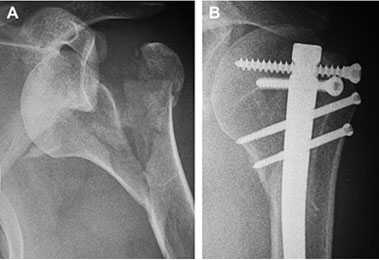

Рис4 а. на рентгенограммах перелом плечевой кости, остеосинтез штифтом и винтами, б. схематическое изображение остеосинтеза пластиной и винтами.

Если необходимо хирургическое лечение, выполняется остеосинтез или эндопротезирование. При остеосинтезе для фиксации отломков применяются металлические конструкции: пластины, винты, штифты. Специалист выполнит точную репозицию отломков и надежную фиксацию. После лечения функция руки полностью восстанавливается.

Рис. 5. а . На рентгенограммах: оскольчатый перелом плечевой кости; б. тотальное эндопротезирование плечевого сустава реверсивным эндопротезом.